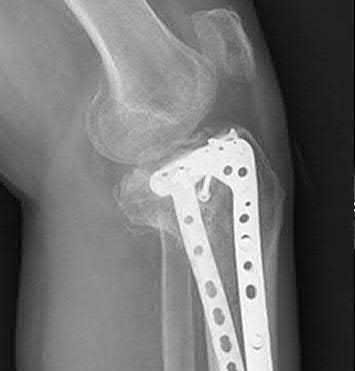

A 51-year-old carpenter presents with a distal humerus nonunion (Figures A and B). After repair of the nonunion, he is lost to follow up for 3 months and then presents to your clinic pain-free and with evidence of fracture union. On examination the elbow arc of motion is 10-80 degrees. Following a brief failed trial of conservative management, you recommend:

Limited flexion outside a functional range of motion (30-130 degrees) can be quite debilitating, and it is often addressed with open release of the posterior bundle of the MCL and posterior capsule and excision of osteophytes.

A frequent complication of distal humerus fractures is post-traumatic stiffness. This patient has had multiple procedures about the distal humerus, and the question stem implies that he did not complete a structured range of motion protocol following the repair of his nonunion. Beyond a trial of conservative management, there are many techniques described for capsule and soft tissue releases as well as bony resections if heterotopic ossification is present. This patient's severely limited flexion would best be addressed with a release of the posterior bundle of the MCL, and with flexion